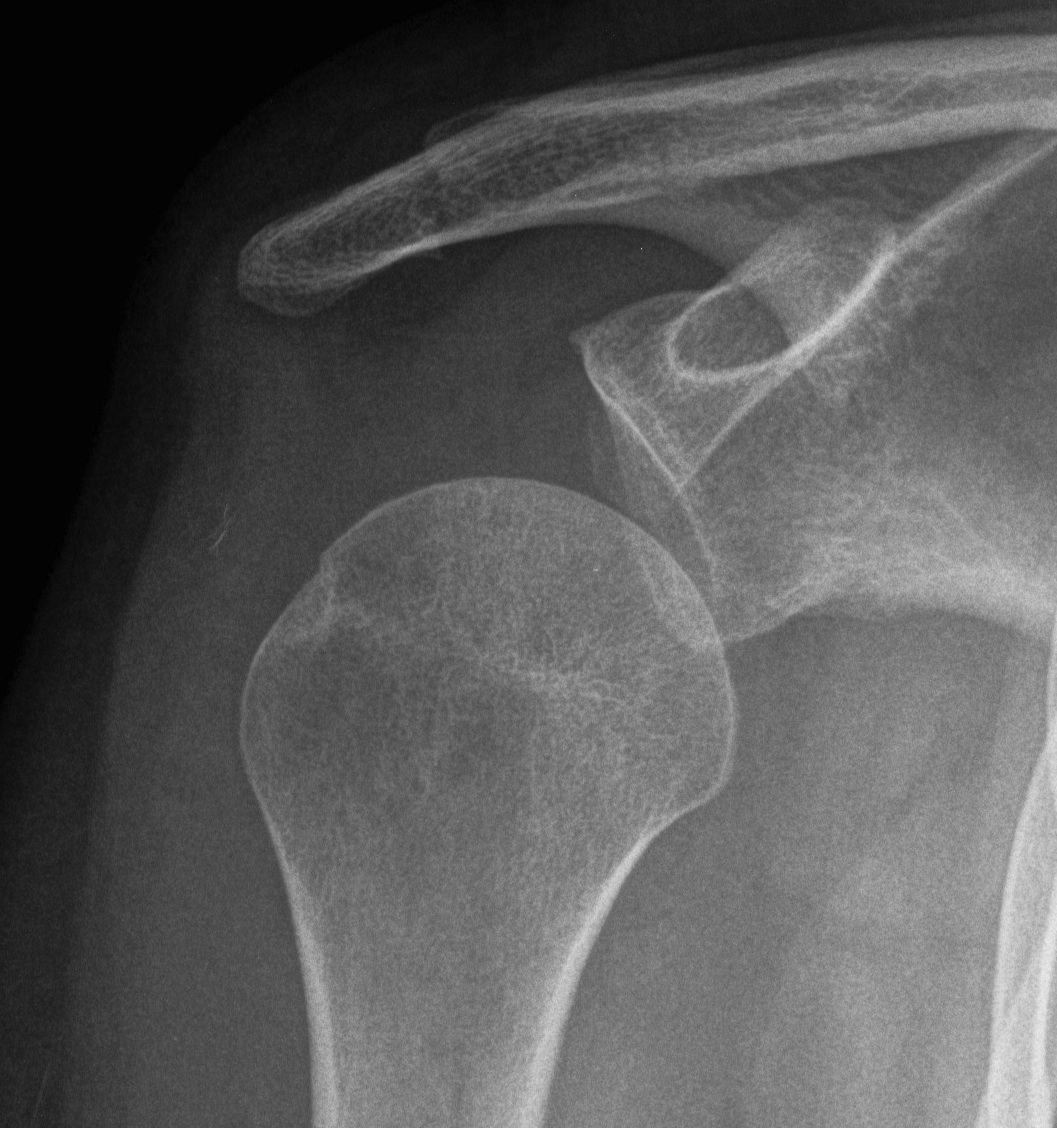

CT

Assess bone stock / glenoid bone loss / Hill Sachs lesions

Chronic shoulder dislocation with large Hill Sachs and minimal glenoid deficiency

Chronic shoulder dislocation with large Hill Sachs and significant glenoid deficiency